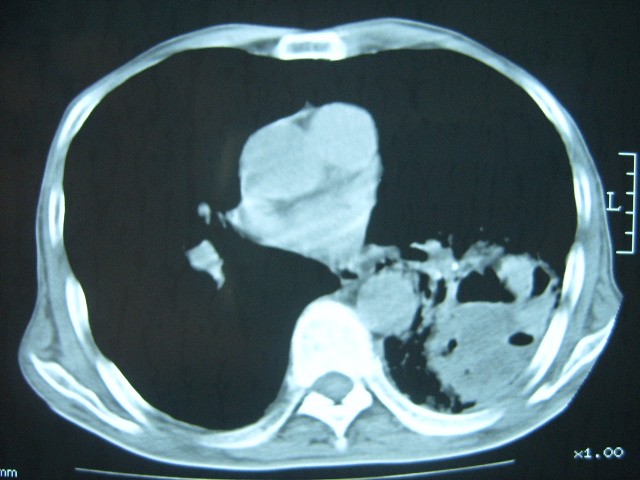

男74岁,咳嗽,寒战,低烧。有糖尿病史。

糖尿病并发肺脓肿建议治疗后复查

考虑:糖尿病合并:1、左下肺炎继发肺脓肿;

2、双肺结核。

两肺慢性炎症伴脓肿形成,不除外继发霉菌感染。

两肺结核,左下肺大片实变,内见空洞性病变,壁不规则,结合糖尿病史,考虑:结核性?霉菌性?建议结合实验室检查或治疗后复查。